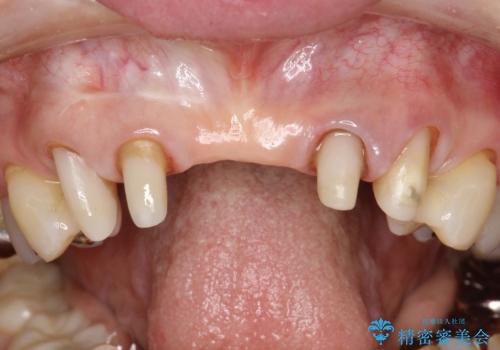

- 仮歯の製作、古い土台(メタルコア)の除去まで行い、根管治療は専門医に依頼

→根管治療終了後、ファイバーコアを築造し、新しいセラミックブリッジを製作した。

一見きれいにはいっているセラミックも、はずして中の状態をみるとひどいことが多い。これは、中の土台の状態や処理のクオリティは、短期的には問題を起こしづらく、患者さんには見えない部分だからです。